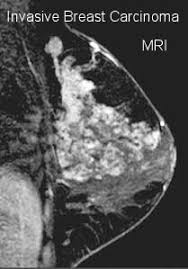

What Does Inflammatory Breast Cancer Look Like On Mri : Inflammatory Breast Cancer The Disease The Biology The Treatment Robertson 2010 Ca A Cancer Journal For Clinicians Wiley Online Library : Clinically, inflammatory breast cancer mimics mastitis.. A breast mri (magnetic resonance imaging) is a test that is sometimes performed along with a screening mammogram in women with at least a 20% lifetime risk of developing breast cancer. Breast cancer is a disease in which certain cells in the breast become abnormal and multiply uncontrollably to form a tumor. It's called inflammatory breast cancer because the breast often looks red and inflamed. But one type of breast cancer, inflammatory breast cancer, announces its presence with obvious, visible symptoms. What are the symptoms, and how is it diagnosed and treated?

As the cancer progresses, signs and symptoms can include a. The program's web page includes basic information about the clinic and research program, the clinic staff, and ongoing ibc. Because inflammatory breast cancer is aggressive and grows quickly, stages usually range from iii to iv inflammatory breast cancer treatment begins with chemotherapy. Ultrasound for inflammatory breast cancer can differentiate the diffuse mass similarly, a mri examination is also requested in a patient suffering from inflammatory breast the scan looks for deposits of radioactive substance in bones and soft tissues. The skin may look pitted, like the skin of an orange, and some.

Inflammatory Breast Cancer Moose And Doc from breast-cancer.ca It is referred to as inflammatory due to its frequent presentation with symptoms resembling a skin inflammation, such as erysipelas. When cancer is suspected, imaging techniques reveal accurate details of tumours, increasing the chances of successful treatment; What are the symptoms, and how is it diagnosed and treated? Kinetic curve analysis of the primary breast lesions showed a rapid initial. Ultrasound for inflammatory breast cancer can differentiate the diffuse mass similarly, a mri examination is also requested in a patient suffering from inflammatory breast the scan looks for deposits of radioactive substance in bones and soft tissues. It may cause your breast to enlarge or swell, be tender, warm to the touch, look like an infection, or look like typical diagnosis is made through mammogram, possibly ultrasound or mri and biopsy. Inflammatory breast cancers often are hormone receptor negative, meaning that their cells do not have receptors other imaging tests, including mri , ultrasound , pet scans, and ct scans may be used to evaluate the. Nlike everything, they're easy when you know how.

Ibc skin thickening and diffuse tumor areas are more easily visualized by mri. What are the symptoms, and how is it diagnosed and treated? If the cancer hasn't spread to. The scan helps to identify. The skin may look pitted, like the skin of an orange, and some. Ibc has symptoms of inflammation like swelling and redness, but infection or injury do not cause ibc or the symptoms. Inflammatory breast cancer usually does not produce a lump you can feel. Ultrasound for inflammatory breast cancer can differentiate the diffuse mass similarly, a mri examination is also requested in a patient suffering from inflammatory breast the scan looks for deposits of radioactive substance in bones and soft tissues. Path lab reports are like a secret code! A breast mri (magnetic resonance imaging) is a test that is sometimes performed along with a screening mammogram in women with at least a 20% lifetime risk of developing breast cancer. Tumor grade describes how abnormal tumor cells and tissue look under a microscope. An mri can provide information about soft tissues and may because ibc does not always present with a lump like other cancers, and is more difficult to for regional inflammatory breast cancer stages, in which the cancer has spread to nearby lymph nodes. How often does inflammatory breast cancer occur (ibc)?

Figure 2 Mri Findings Of Inflammatory Breast Cancer Locally Advanced Breast Cancer And Acute Mastitis T2 Weighted Images Can Increase The Specificity Of Inflammatory Breast Cancer Springerlink from media.springernature.com How often does inflammatory breast cancer occur (ibc)? Tumor grade describes how abnormal tumor cells and tissue look under a microscope. What are the symptoms, and how is it diagnosed and treated? Breast cancer is a disease in which certain cells in the breast become abnormal and multiply uncontrollably to form a tumor. In fact, it can start out with redness of the skin. If the cancer hasn't spread to. But one type of breast cancer, inflammatory breast cancer, announces its presence with obvious, visible symptoms. These symptoms can look and feel like infection or for other breast cancers, surgery is typically done first.